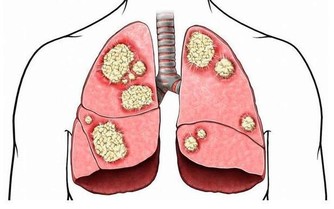

法國一項研究發現,小腿圍小於33公分的女性,患有頸動脈斑塊的風險相對更高,而這是中風的一個已知風險因素。小腿肚上的皮下脂肪會提升並儲存能夠促進血液循環的脂肪酸,以避免頸動脈斑塊形成。